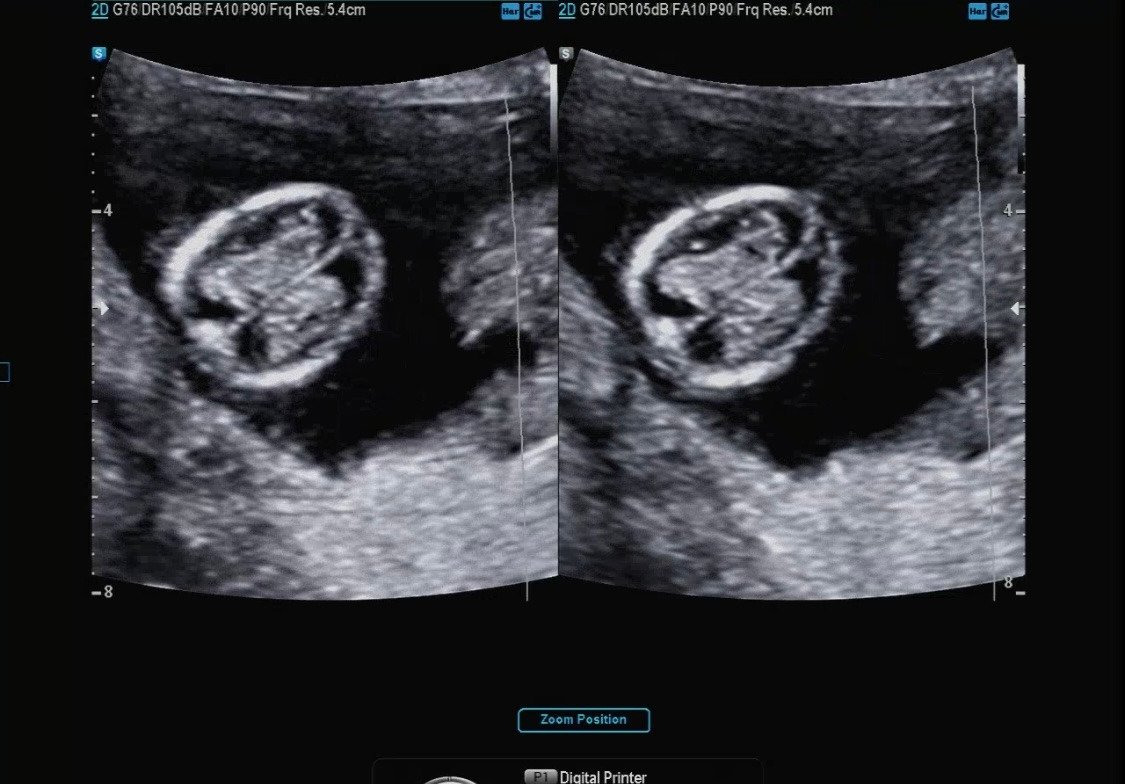

아가 사이즈 측정

머리에서 엉덩이까지의 길이

12주 차 3일 12주 차 4일이 나왔고, 원래 7일 정도의 차이는 존재한다고 알려주셨다.

사이즈는 6cm 정도로 컸더라 :)

딱 12주 차는 5.4의 자두 정도의 크기라고 베이비빌리를 통해 알고 있었다. 아마 12주 차 2일에 방문해서 아가가 조금 더 큰 거 같다. 하루하루 다르게 쑥 쑥 크고 있는 다올이의 모습이 참 신기하다.